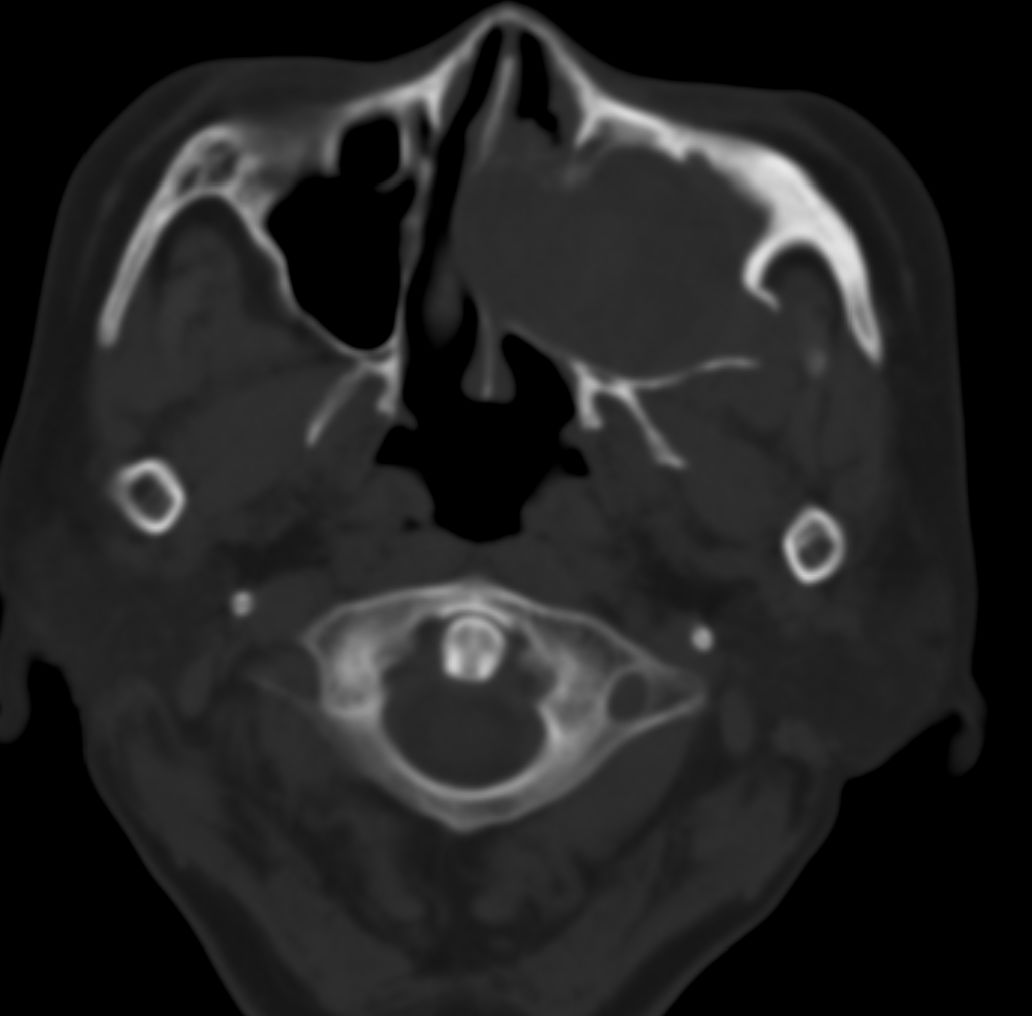

女,69岁。鼻出血2月多。(会诊病史就这样简单)鼻副窦ct检查如下:

左侧鼻腔及上颌窦见软组织块影,左侧上颌窦腔扩大,骨质吸收,右侧上颌窦见半圆形软组织密度影,鼻中隔向右侧弯曲,左侧鼻和鼻窦内翻型乳头状瘤可能性大,建议增强。

左侧上颌窦及鼻腔内见软组织密度影,其内密度不均匀,见斑片状高密度影,右侧上颌窦腔明显扩大,窦壁吸收变薄,鼻中隔右偏,右侧上颌窦见一半圆形软组织密度影,边界清楚,其内密度均匀。诊断,1、左侧鼻腔及上颌窦内翻乳头状瘤可能性大,上颌窦癌,息肉及霉菌性上颌窦炎待除外。2、右侧上颌窦粘膜下囊肿。

1)考虑左侧上颌窦内翻乳突状瘤突入左侧鼻腔。2)副鼻窦炎,右侧上颌窦黏膜下囊肿。

病理:霉菌性左侧上颌窦炎伴左侧上颌窦纤维组织增生。

窦腔密度不均匀增高,无明显钙化征象,后外侧及内侧窦壁膨胀明显,局部破坏消失,筛窦受累及,但双侧对比发现左侧窦壁骨质有硬化增白现象,这可能是支持左侧霉菌性上颌窦炎的主要依据点。